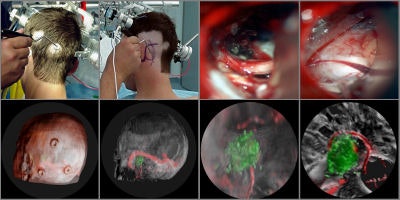

Intraoperative navigation

Intraoperative navigation uses both preoperative images (CT and MR) and intraoperative images (ultrasound and video) to provide localization information during surgery. The main challenge involved in surgical navigation is the registration of the preoperative data with the surgical environment -- that is, with the patient and the surgical instruments. Until now, the usage of 3D imaging during surgery has been limited due to the lack of computation power needed to produce real-time images.

Today, numerous systems augment the surgeon's vision during surgery by providing for the real-time fusion of preoperative volumetric data with intraoperative data, such as video, ultrasound, and images from a surgical microscope and endoscope. Other systems enhance intraoperative visualization by providing feedback regarding the location of the surgical instruments with respect to preoperative data. They use optical or mechanical sensors to localize instruments in the operating room, then map them onto the preoperative images (see figure 7, below).

![]() |

| Figure 7 |